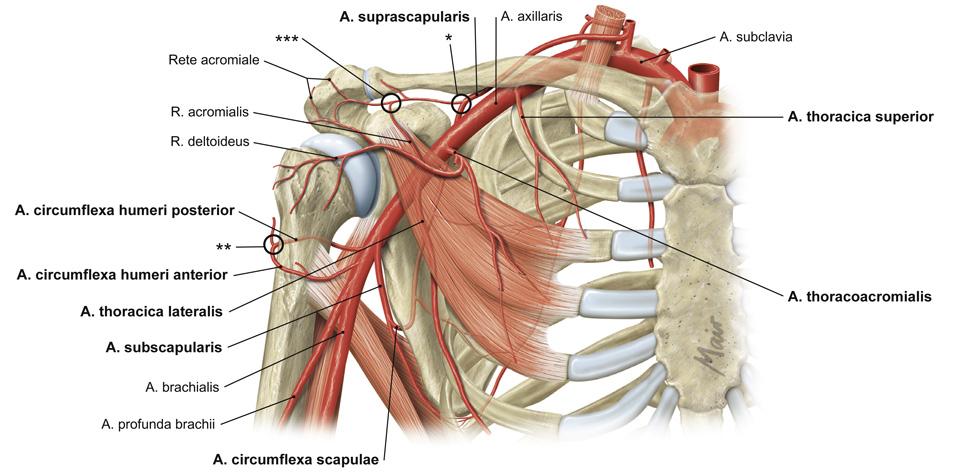

Fig 3.17: a. axillaris

-

scapula

-

humerus

tuberculum maius tuberculum minus crista tuberculi maioris crista tuberculi minoris collum chirurgicum

m pectoralis minor (geel) m pectoralis maior (geel) a thoracoacromialis a thoracica lateralis -

a subscapularis

a cx. scapulae a thoracodorsalis

a cx. humeri posterior (samen met n. axillaris door laterale okselpoort) a cx. humeri anterior a brachialis (vanaf onderrand m. pectoralis maior)

|